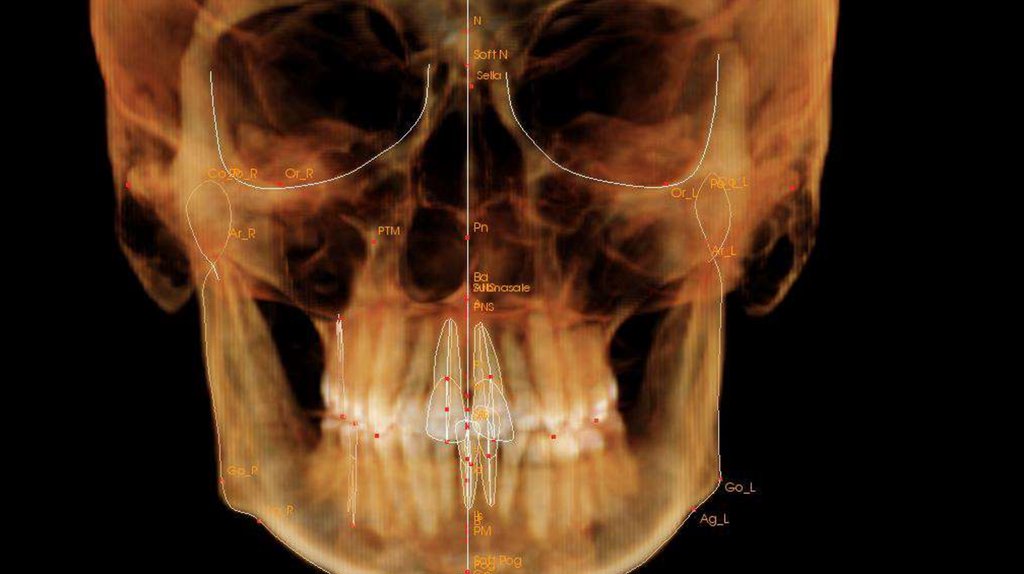

По рассчетам снимков:

• Ретрузия резцов верхней челюсти

• Компрессия головок суставов, особенно правого( началось

ремоделирование)

• Костная ассиметрия(10 мм)

• 2 класс

• 25, 46 зуб – нуждается в санации

• Требуется профессиональняа гигиена полости рта

• Клиновидные дефекты 43, 44

• 18, 28, 38, 48 отсутствуют.

Скелетный: II класс.